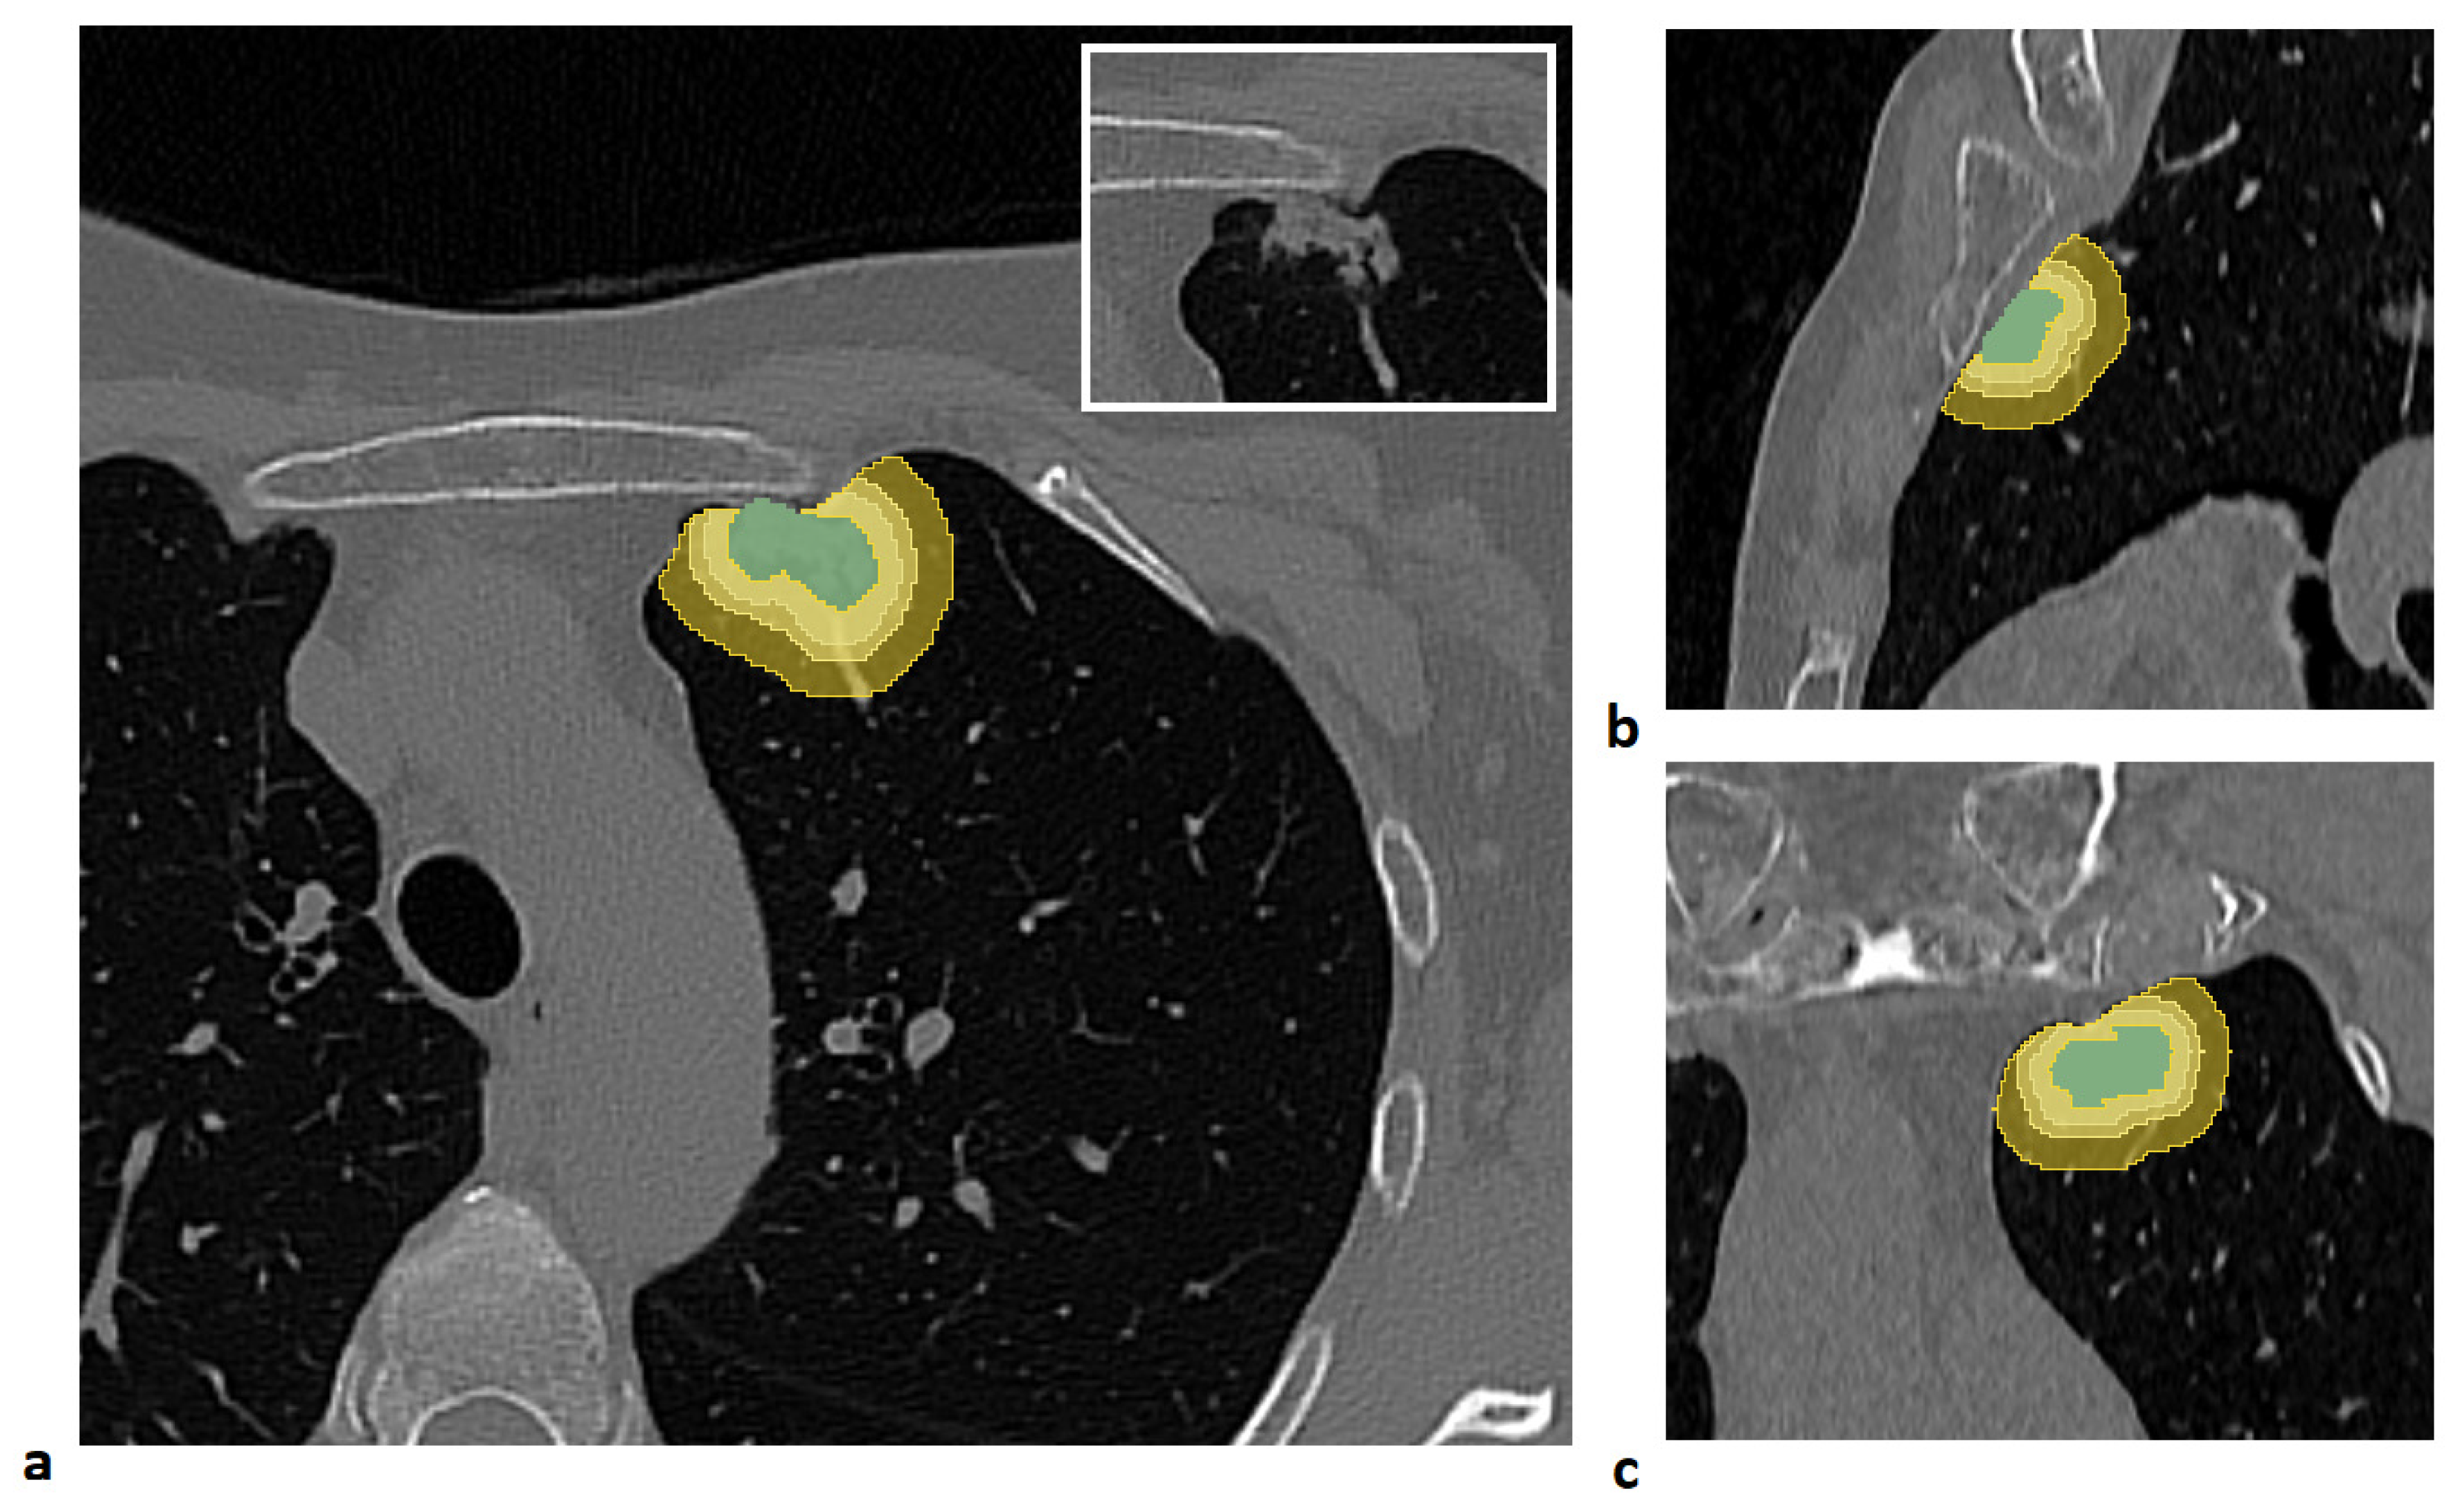

For each patient, four distinct volumes of interest (VOIs) were analyzed: the lung lesion and its peritumoral regions obtained by expanding the lesion margins by 3 mm, 5 mm, and 10 mm. The lesion was manually segmented slice by slice by an expert radiologist using semi-automatic tools in the 3D Slicer software (version 5.8.1) [16].

To generate the peritumoral regions, the entire lung volume was first automatically segmented using the Lung CT Segmenter extension in 3D Slicer software. Peritumoral VOIs were then generated using a custom MATLAB script (Release R2021b, MathWorks Inc., Natick, MA, USA). First, an isotropic kernel was applied to each manually segmented lesion to create isotropic expansions of 3 mm, 5 mm, and 10 mm around the tumor. Then, to ensure that the expanded volumes remained confined to the lung parenchyma, each expansion was intersected with the previously segmented lung mask. Finally, the lesion volume was subtracted from each expanded VOI to isolate only the peritumoral tissue.

An example of a segmented lesion and the corresponding peritumoral regions is shown in Figure 1.

Figure 1. Example of lesion segmentation and the corresponding peritumoral regions generated by isotropic expansions of 3 mm, 5 mm, and 10 mm, constrained within the lung parenchyma mask, shown in the axial (a), sagittal (b), and coronal (c) views. The lesion is shown in the box at the top right of panel (a).